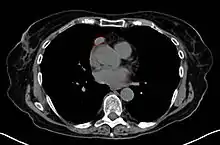

Міастенію встановлюють на підставі анамнестичних даних, клінічного огляду, позитивної проби з антихолінестеразними препаратами, електроміографічного обстеження, динамічного спостереження. При зборі анамнезу звертають увагу на мінливість симптомів протягом доби, зв'язок їх з навантаженням, наявність часткових або повних ремісій, зворотність симптомів на тлі вживання антихолінестеразних препаратів (на час їх дії) і на тлі адекватної імуносупресивної терапії. Специфічним тестом для діагностики міастенії є проба з антихолінестеразними препаратами: прозерином, каліміном. Найчастіше проводять пробу з прозерином (неостигміном). Дозу підбирають індивідуально з розрахунку 0,125 мг/кг маси тіла. Можна вибрати будь-який парентеральний шлях введення препарату, але зазвичай проводять підшкірну ін'єкцію. Оцінюють дію препарату через 30-40 хвилин. Позитивною пробу вважають при відновленні м'язової сили з компенсацією бульбарних і окуломоторних порушень. У діагностично складних випадках проводять морфологічне дослідження м'язового біоптату (світлова, електронна мікроскопія, гістохімічне, імуногістохімічне, імунофлюоресцентне та інші види візуального вивчення нервово-м'язових з'єднань і оточуючих їх тканин). Поряд з різними клінічними, електрофізіологічними, фармакологічними методами для уточнення діагнозу міастенія використовують й імунологічні методи (імуноферментні, радіоімунологічні), що полягають в кількісному визначенні анти-АХ-автоантитіл у сироватці крові хворих, що дозволяє з імовірністю до 80 % підтвердити цей діагноз.